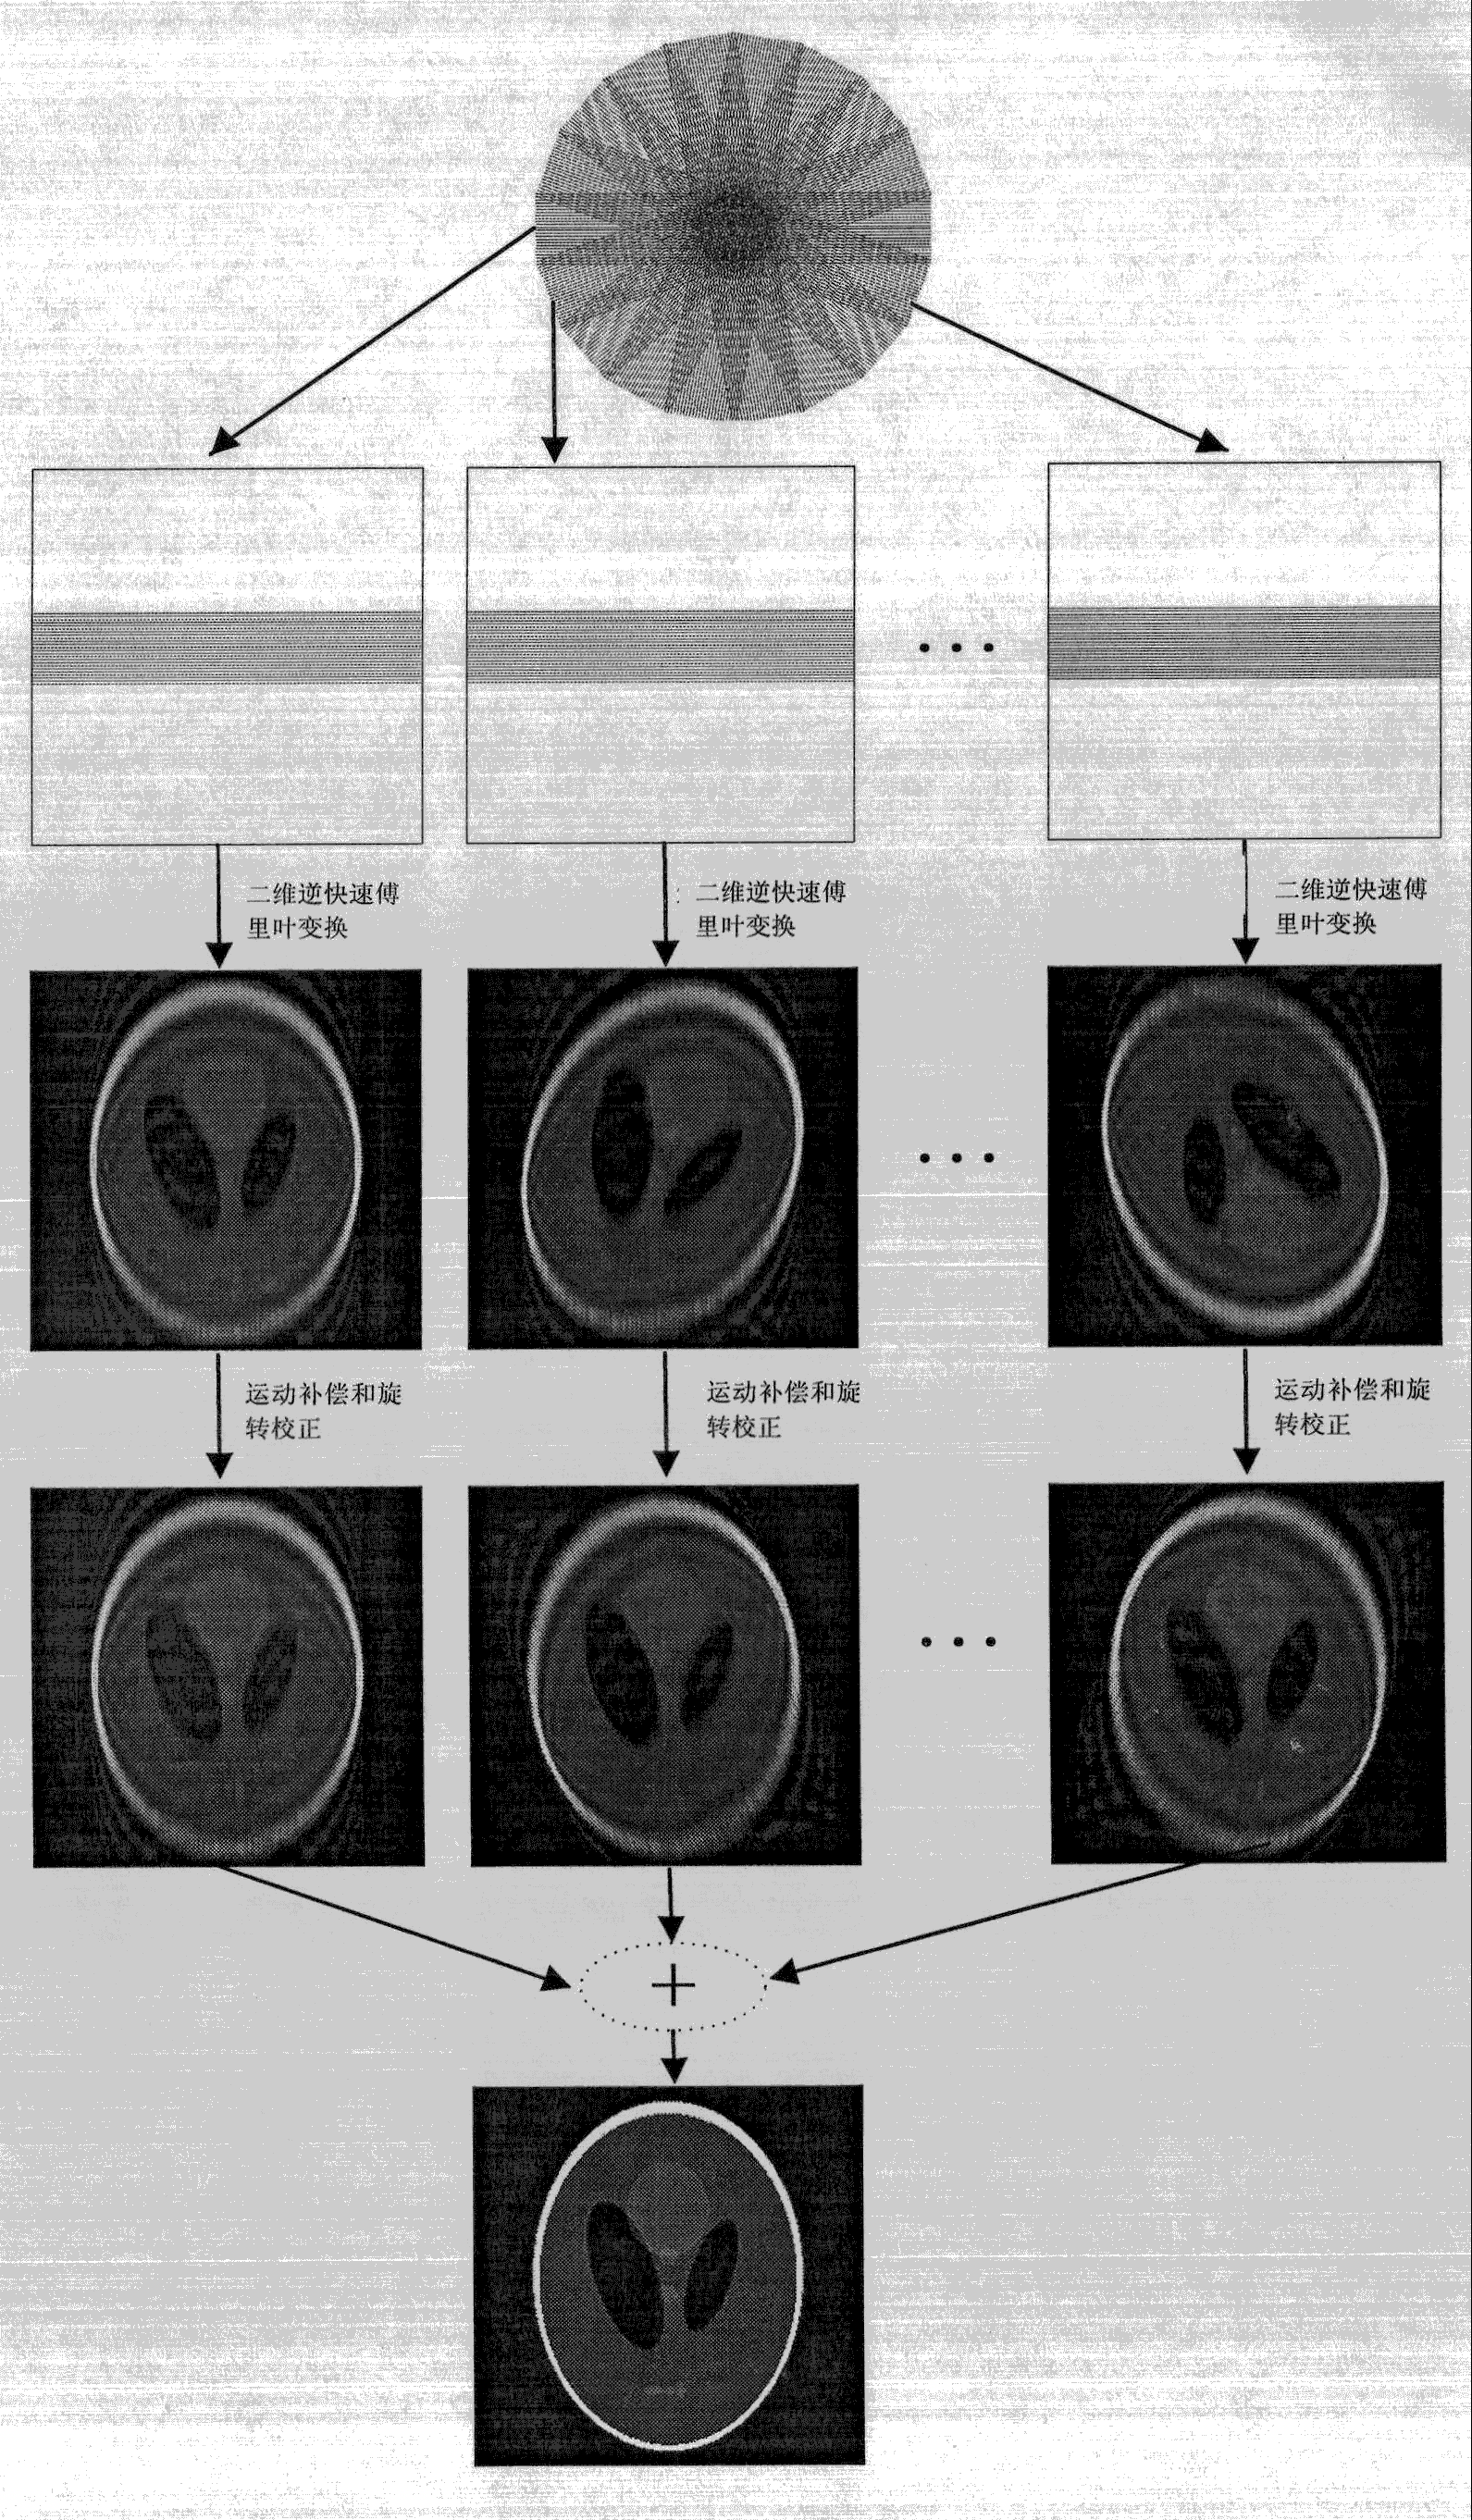

| 摘要: | 本发明公开了一种基于图像域叠加的PROPELLER磁共振数据重建方法,包括以下步骤:(1)基于PROPELLER采集方式采集磁共振数据;(2)对每个K空间条进行密度补偿后进行二维逆快速傅里叶变换重建出临时图像;(3)在图像域对临时图像进行运动补偿和旋转校正;(4)将校正后的临时图像叠加得到最后的重建结果。该磁共振数据重建新方法可以有效的避免混迭伪影的干扰,获得更高的图像重建精度。 | ||||